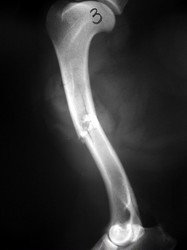

PRÁCTICAS CURSO DE FIJACIÓN EXTERNA PERFECCIONAMIENTO.

Húmero.